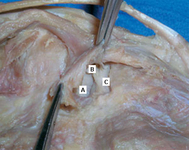

Popliteal cyst lying in its most common location in the posteromedial popliteal fossa (A), dissecting through the deep fascia (B) and the medial head of the gastrocnemius muscle (C)

Adapted from Labropoulos N, Shifrin DA, Paxinos O. New insights into the development of popliteal cysts. Br J Surg. 2004;91:1313-1318; used with permission

Deep dissection of the posteromedial capsule. The two expansions of the semimembranosus muscle have been elevated, exposing the weak area of the capsule between the posterior cruciate ligament (A) and the posterior horn of the medial meniscus (B) that gives entry to the knee joint. The medial femoral condyle is also visible (C)